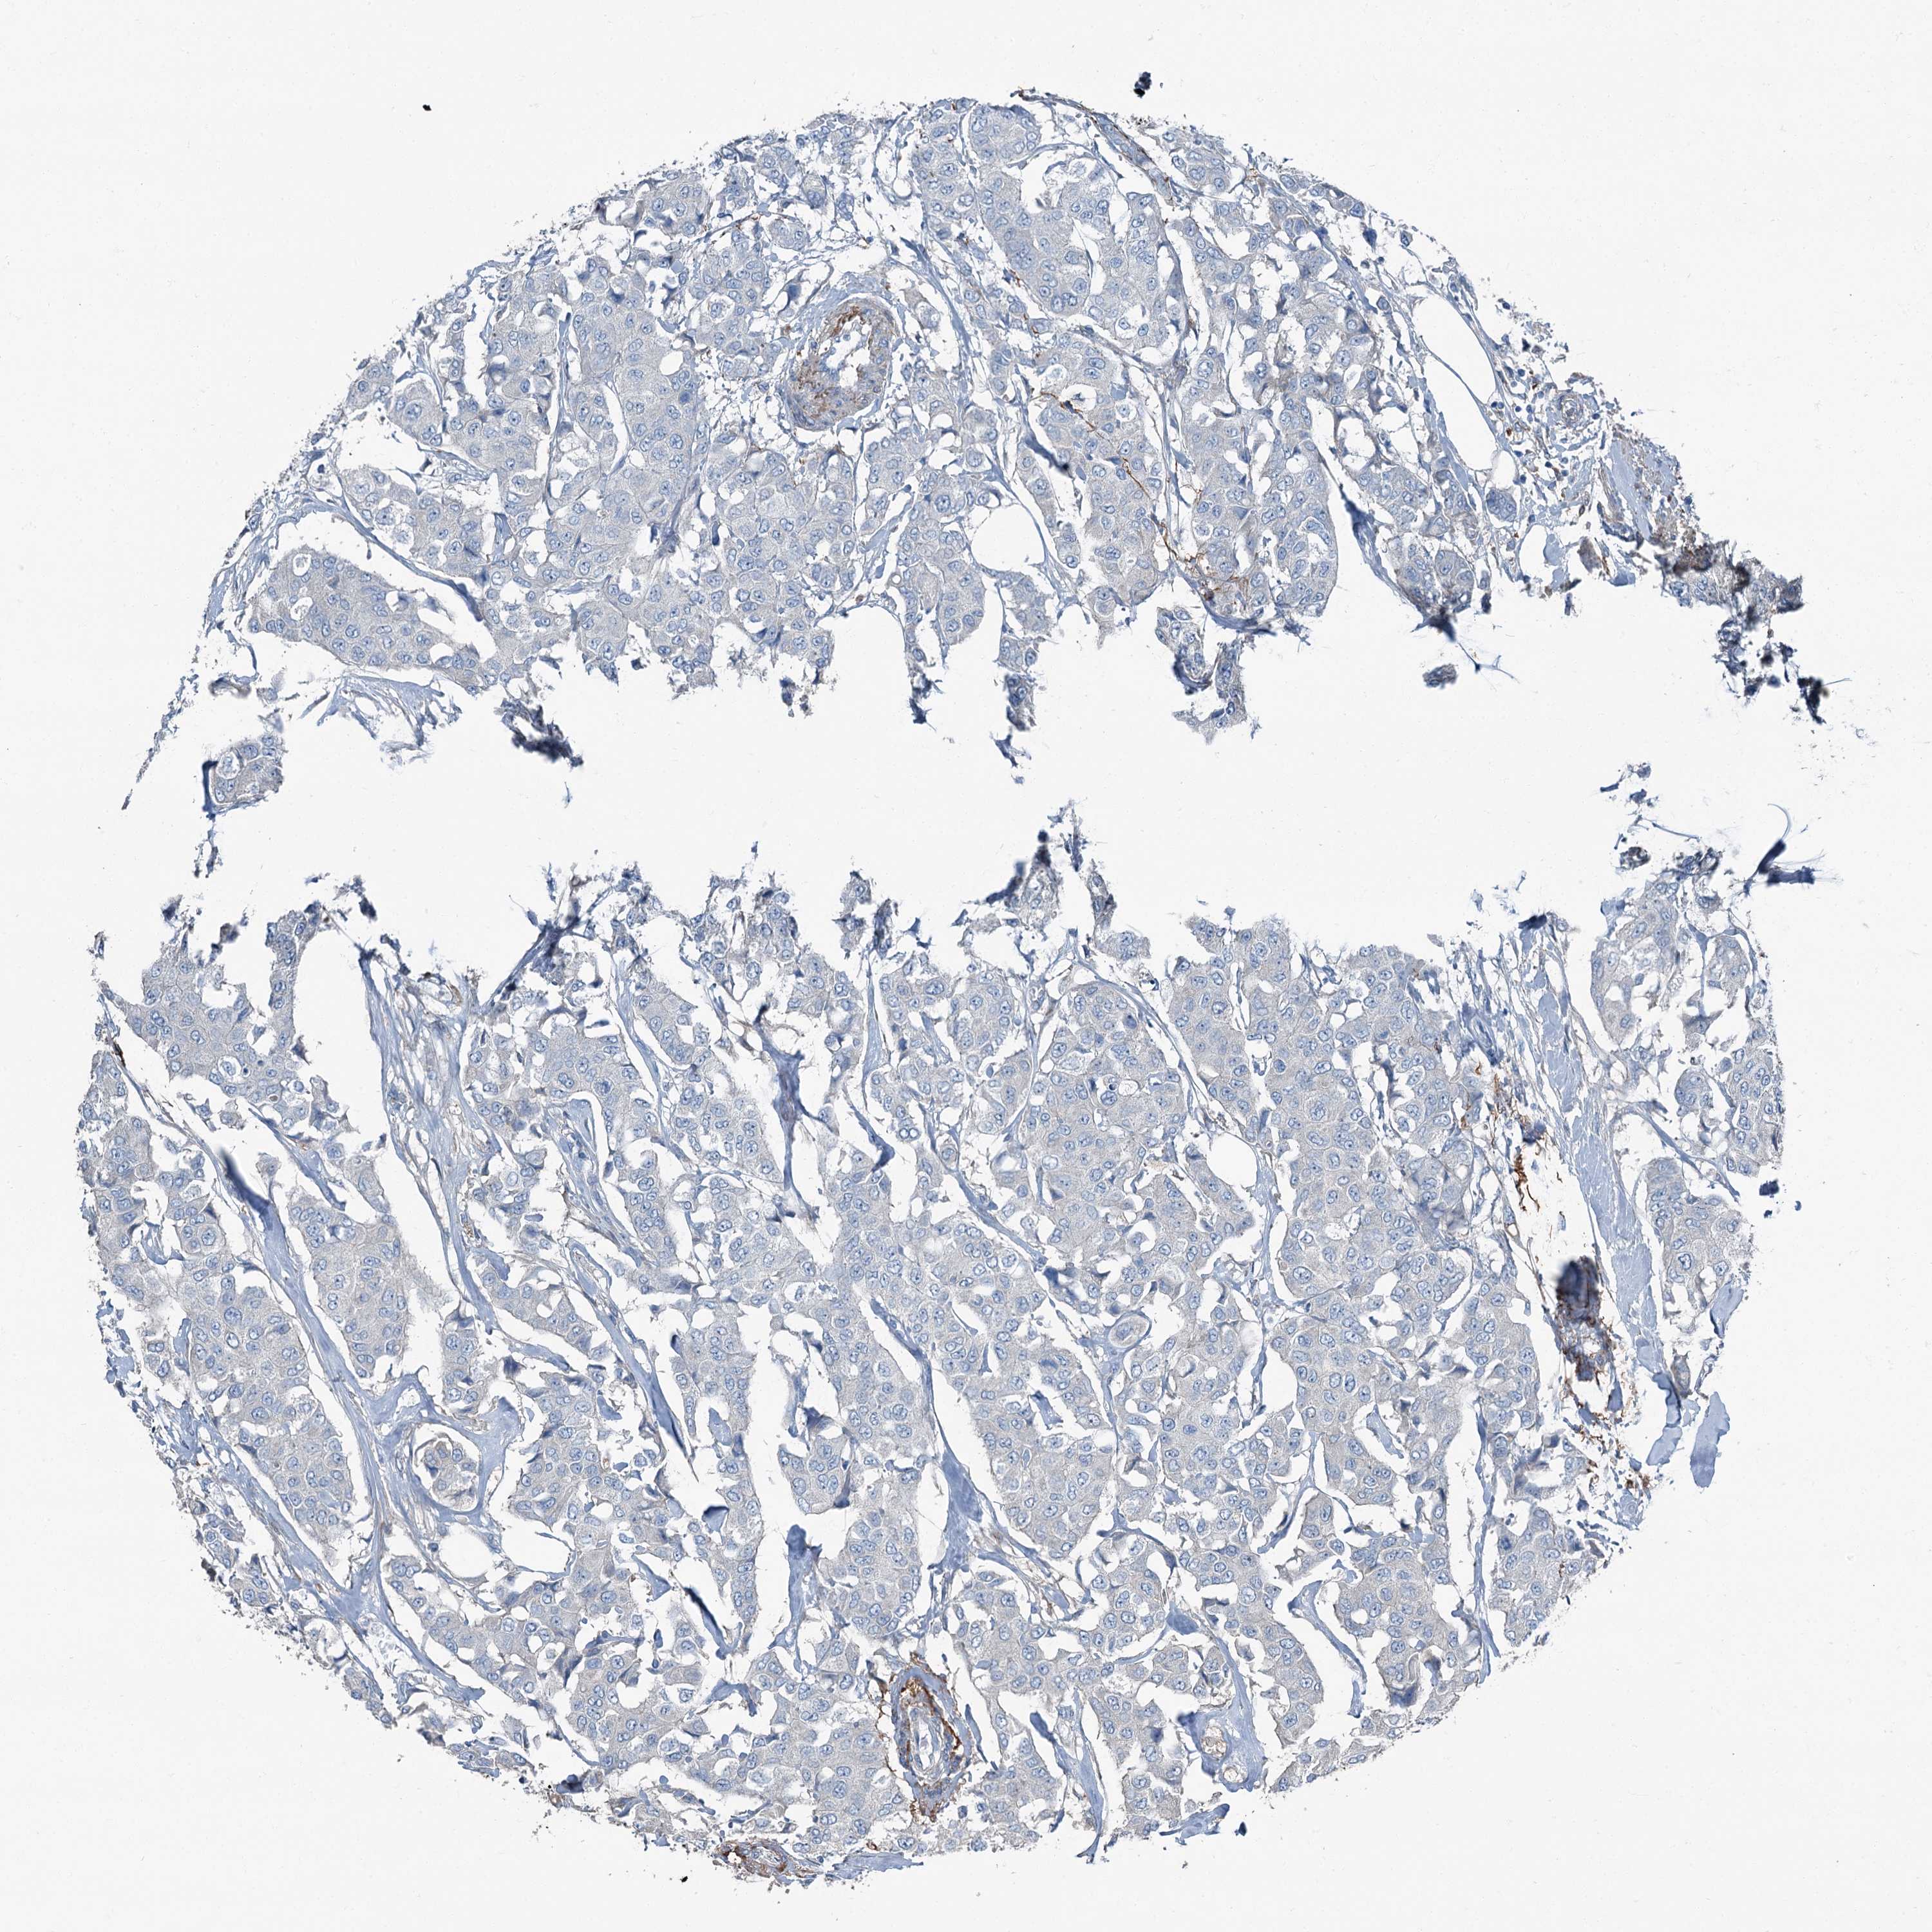

BRCA TCGA BRCA VALIDATION PROTEIN EXPRESSION